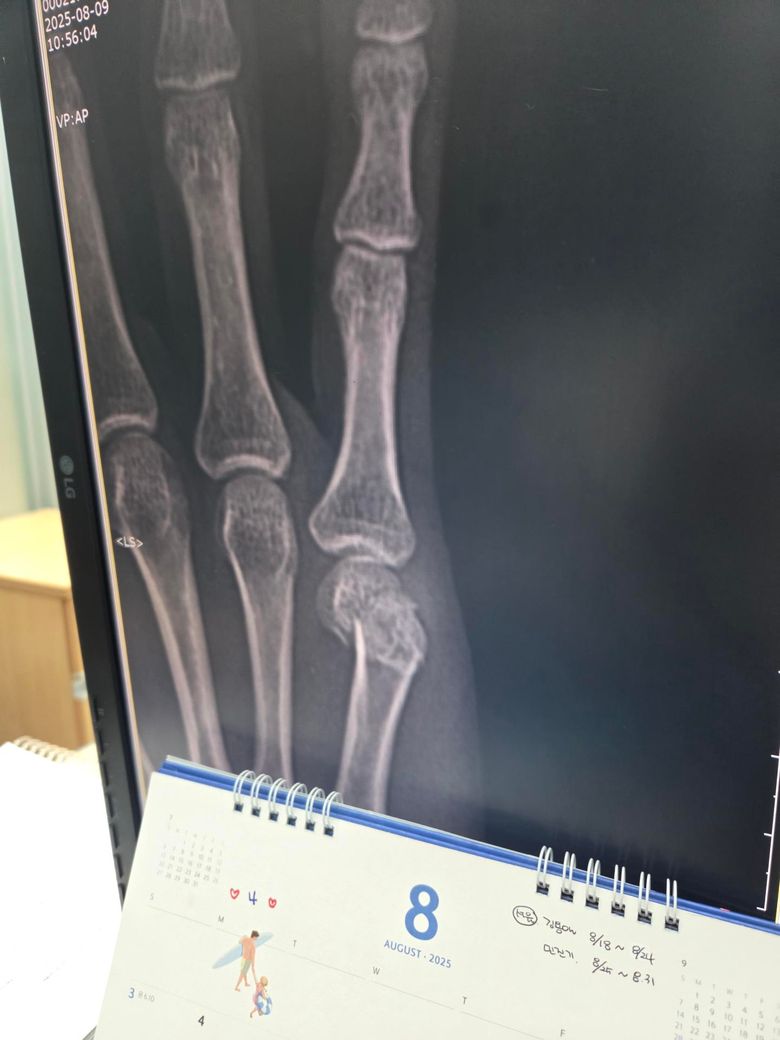

두 번째 사진을 보시면 수술한 손가락이 다른 손가락에 비해 뼈가 잘 정렬이 안 된 것 같아서요. 수술적으로 잘못된 부분이 있는지 알려주시면 감사하겠습니다.

• 2번 째 사진

제가 직접적으로 수술의 판단해 드리긴 어렵습니다. 다만 사진상으로는 금속 핀 고정으로 뼈 정렬을 잡은 흔적이 보이며 수술 직후에는 약간의 틀어짐이 있어도 시간이 지나면서 유합과정에서 교정되는 경우가 많습니다.

뼈가 완벽히 일직선으로 맞지 않아도 기능 회복에는 큰 지장이 없는 경우도 흔합니다!